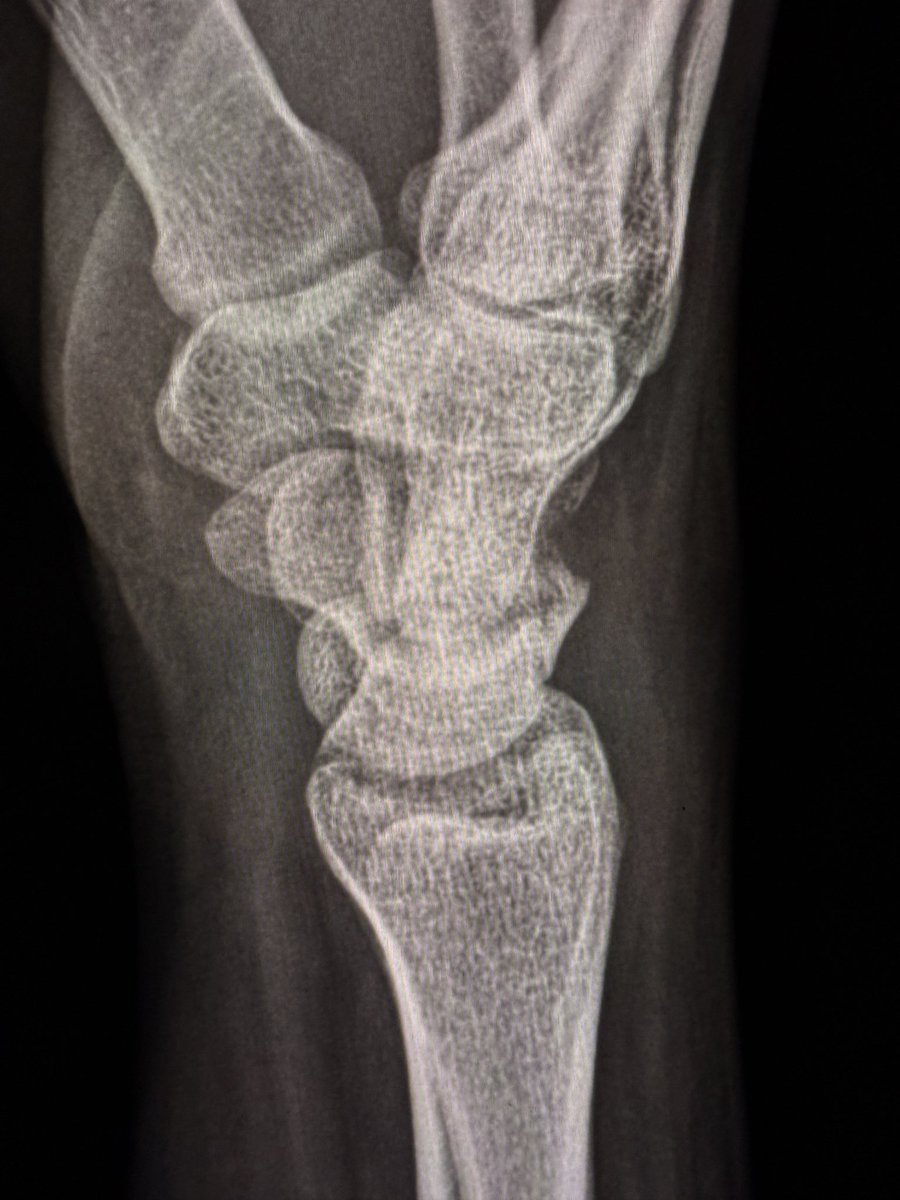

A large dorsal talar beak on sagittal CT or lateral ankle radiograph.

Talar beak is a marker of restricted subtalar motion, not a diagnosis. In a young patient, actively search for a subtalar coalition.

This case showed a fibrous coalition of Medial accessory talocalcaneal articulation at the level of the posterior sustentaculum tali, between the Talus and Calcaneus.

Wisdom: A talar beak should trigger a search, not end it.